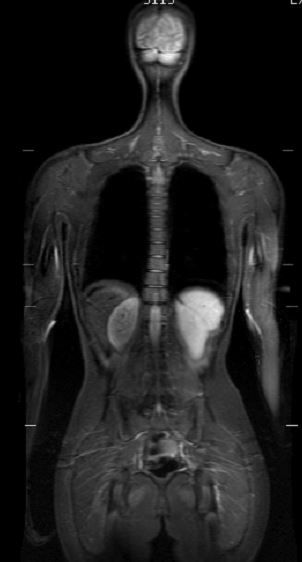

Today's techniques, like MRI (Magnetic Resonance Imaging) and CT (Computed Tomography) scans, offer detailed images of soft tissues and organs. For instance, MRIs can reveal subtle changes in brain structure, while CT scans provide intricate details of internal organs. These advancements have increased diagnostic accuracy, allowing healthcare professionals to detect potentially serious conditions early on.

Each imaging technique comes with distinct benefits. Their combined usage greatly enhances the chance of catching diseases early. For example, mammograms have shown to reduce breast cancer mortality by about 30% in women aged 40 to 74 when part of regular screenings. Similarly, CT scans can detect lung diseases at earlier stages compared to standard X-rays, with sensitivity rates increasing by up to 25% for certain conditions.

The ability to diagnose early is crucial. Research shows that patients with early-stage diseases often have better treatment options, leading to improved survival rates. By using imaging technologies, healthcare providers can identify risk factors and implement targeted preventive measures that can significantly affect patient outcomes.